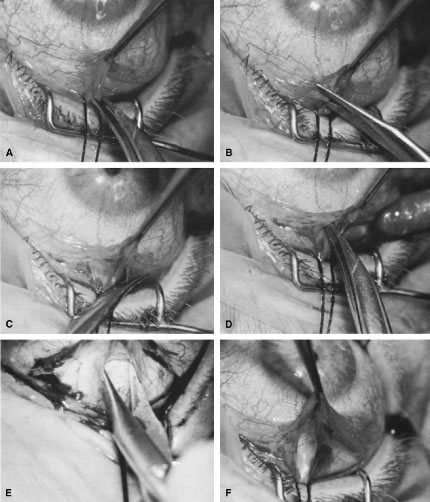

irrigated away, and chamber deepening cannot readily be performed.  Fig. 10. Peripheral iridectomy with the use of a preplaced suture to retract the

edges of the incision. A. An incision is made through two thirds of the thickness of the sclera

directly at the corneoscleral sulcus. B. A 9-0 white virgin silk suture is placed so that it will be able to be

retracted from the depths of the incision. C. The suture is looped and used to retract the edges of the incision superiorly

and inferiorly. The incision is completed, permitting prolapse

of a small knuckle of iris. D. The iris is grasped with a fine-toothed forceps. E. The iris is pulled over the blade of the DeWecker scissors; after the

position of the iris is noted, the blades are closed and the tissue is

excised. F. The tip of an irrigator is placed just inside the incision, with care

taken to ensure that it does not enter the anterior chamber. Remnants

of the pigment epithelium are flushed away, and the iris is permitted

to return to its proper position so that the pupil is completely round. (Spaeth GL. Glaucoma surgery. In Spaeth GL (ed). Ophthalmic Surgery: Principles

and Practice. Philadelphia: WB Saunders, 1990.) Fig. 10. Peripheral iridectomy with the use of a preplaced suture to retract the

edges of the incision. A. An incision is made through two thirds of the thickness of the sclera

directly at the corneoscleral sulcus. B. A 9-0 white virgin silk suture is placed so that it will be able to be

retracted from the depths of the incision. C. The suture is looped and used to retract the edges of the incision superiorly

and inferiorly. The incision is completed, permitting prolapse

of a small knuckle of iris. D. The iris is grasped with a fine-toothed forceps. E. The iris is pulled over the blade of the DeWecker scissors; after the

position of the iris is noted, the blades are closed and the tissue is

excised. F. The tip of an irrigator is placed just inside the incision, with care

taken to ensure that it does not enter the anterior chamber. Remnants

of the pigment epithelium are flushed away, and the iris is permitted

to return to its proper position so that the pupil is completely round. (Spaeth GL. Glaucoma surgery. In Spaeth GL (ed). Ophthalmic Surgery: Principles

and Practice. Philadelphia: WB Saunders, 1990.)